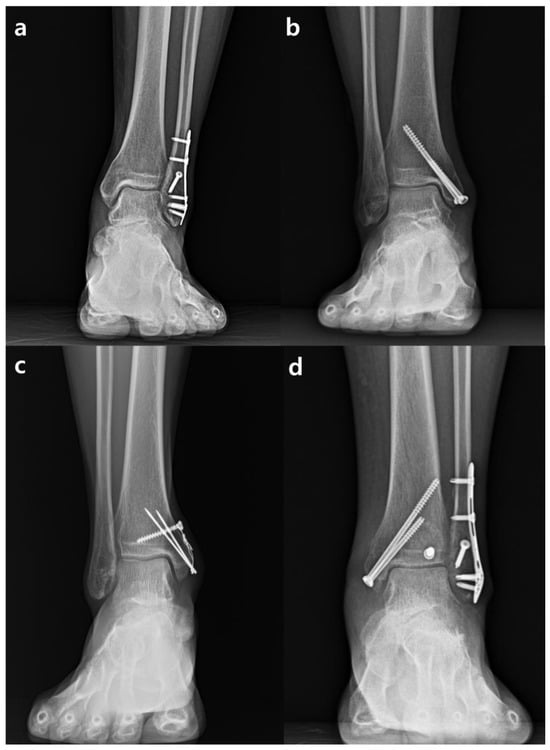

4.1. Surgical Procedures